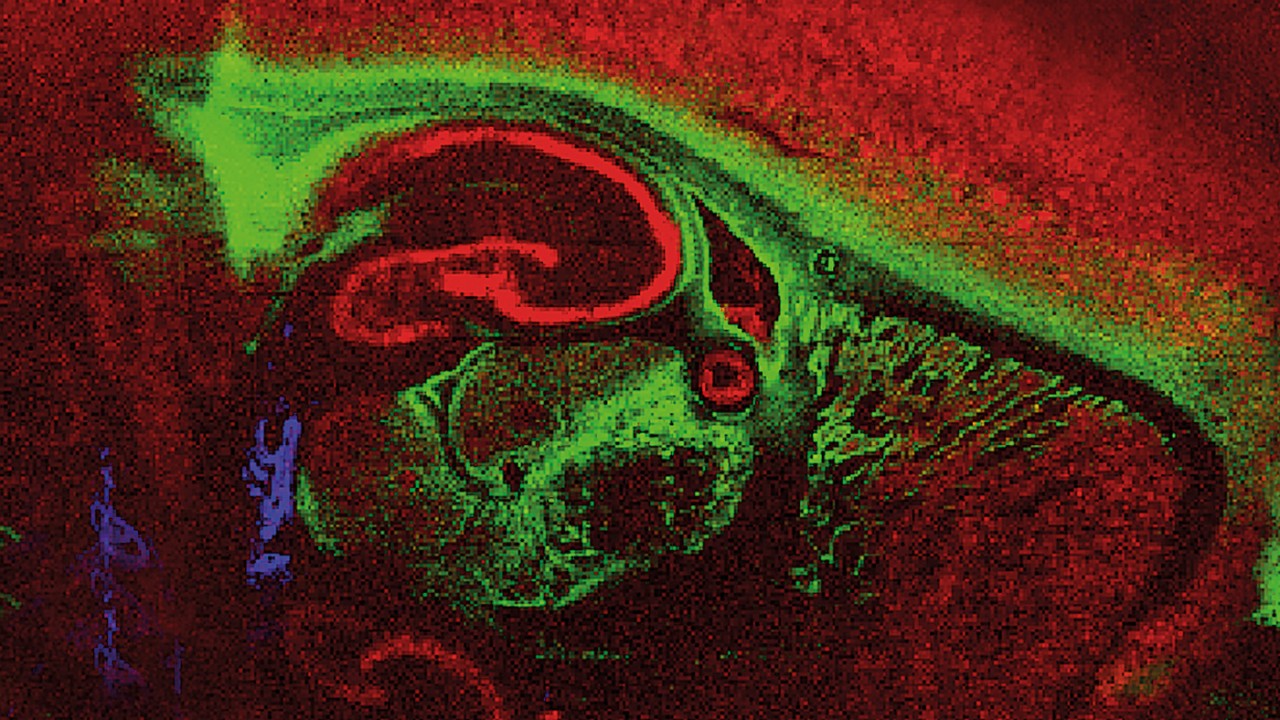

Since the discovery of MALDI in the mid 80's this fast and high-throughput enabling ionization made its way into a variety of applications. The inherent speed of MALDI-TOF analysis from sample to result allows for fast answers to your analytical questions. The laser aiming at different positions gives rise to spatial, molecular information as used e.g. for MALDI Imaging for tissues.